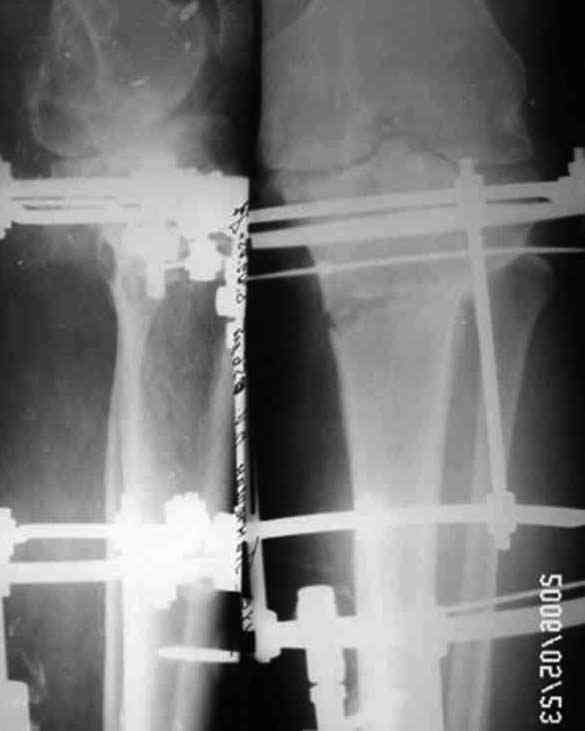

Уважаемые коллеги! Хотелось бы обсудить на форуме ряд вопросов касающиеся оперативного лечения гонартроза и, в частности, высокую остеотомию б/б кости. Работаю в частной клинике ортопедо-травматологического профиля, делаем артроскопические операции, в том числе и при гонартрозах. При варусной деформации сустава выполняем чрез- подбугорковые остеотомии по Илизарову (ВКДО) - как вариант медиальной клиновидной плюс-остеотомии с пересечением латеральной кортикоспонгиозной части кости. Остеотомия (кортикотомия) производится через 1-2 прокола «глазным» долотом (шириной 5 мм) после установки 3 кольцевого гибридного аппарата (спицы 2 мм и стержни 4,5 мм). На крайних кольцах по две спицы с захватом м/б кости, по стержню Шанца в верхнее и среднее кольцо. Пересечение малоберцовой кости производим на протяжении средней трети кости этим же долотом. Первым этапом операции выполняем артроскопическую санацию, дебридмент и т.д. При выращивании клиновидного регенерата центр вращения - наружный кортикалис. Коррекцию начинаем на 5 сутки, завершаем через 10-14 дней. Аппарат снимаем обычно на 45 сутки. Операция непростая, можно ожидать все, что угодно, но очень эффективная. Вопросы: • Возможность применение аутотрансплантата после одномоментного устранения деформации, для того, чтобы не выращивать регенерат и сократить сроки пребывания в стационаре • Возможно, ли выполнение неполной кортикотомии б/б кости с оставлением интактным латерального кортикалиса • Обязательно ли пересечение м/б кости при ВКДО • Есть ли у кого опыт коммерческого лечения больных старше 60 лет с клиникой повреждения менисков на фоне ярко выраженного гонартроза. Наш опыт горький. Прилагаю иллюстрации, Р-граммы - в процессе лечения Попов Виктор, г.Караганда

> опыт горький. Прилагаю иллюстрации, Р-граммы - в процессе лечения